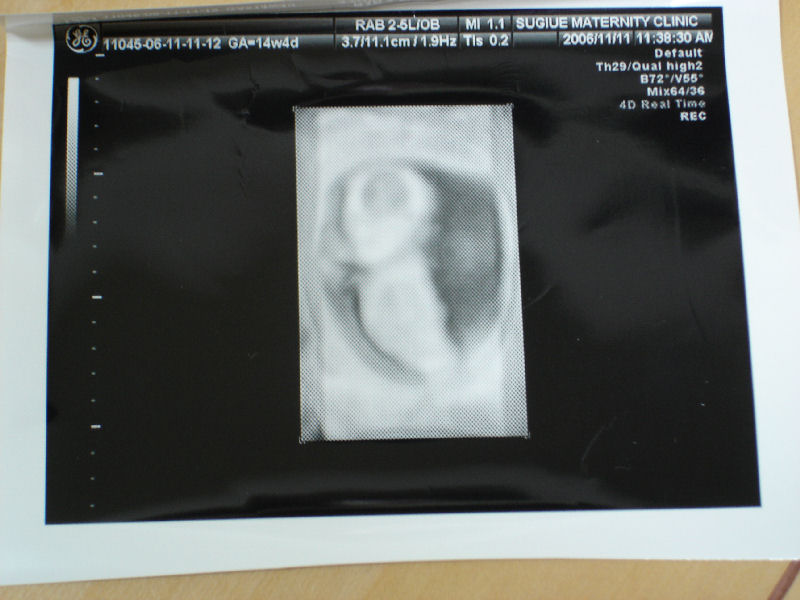

そしてエコー写真を見せてもらった。 1ヶ月ぶりの受診。 どれくらい大きくなったのかな~

体長は15cmだって。 ようやく頭と体と手が判別できるようになった。 これがどんどん大きくなっていくのかな~

楽しみ。